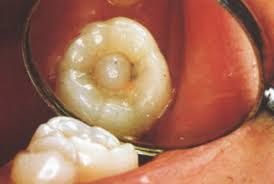

1 ฟันซี่นี้ วินิจฉัยว่าอะไร